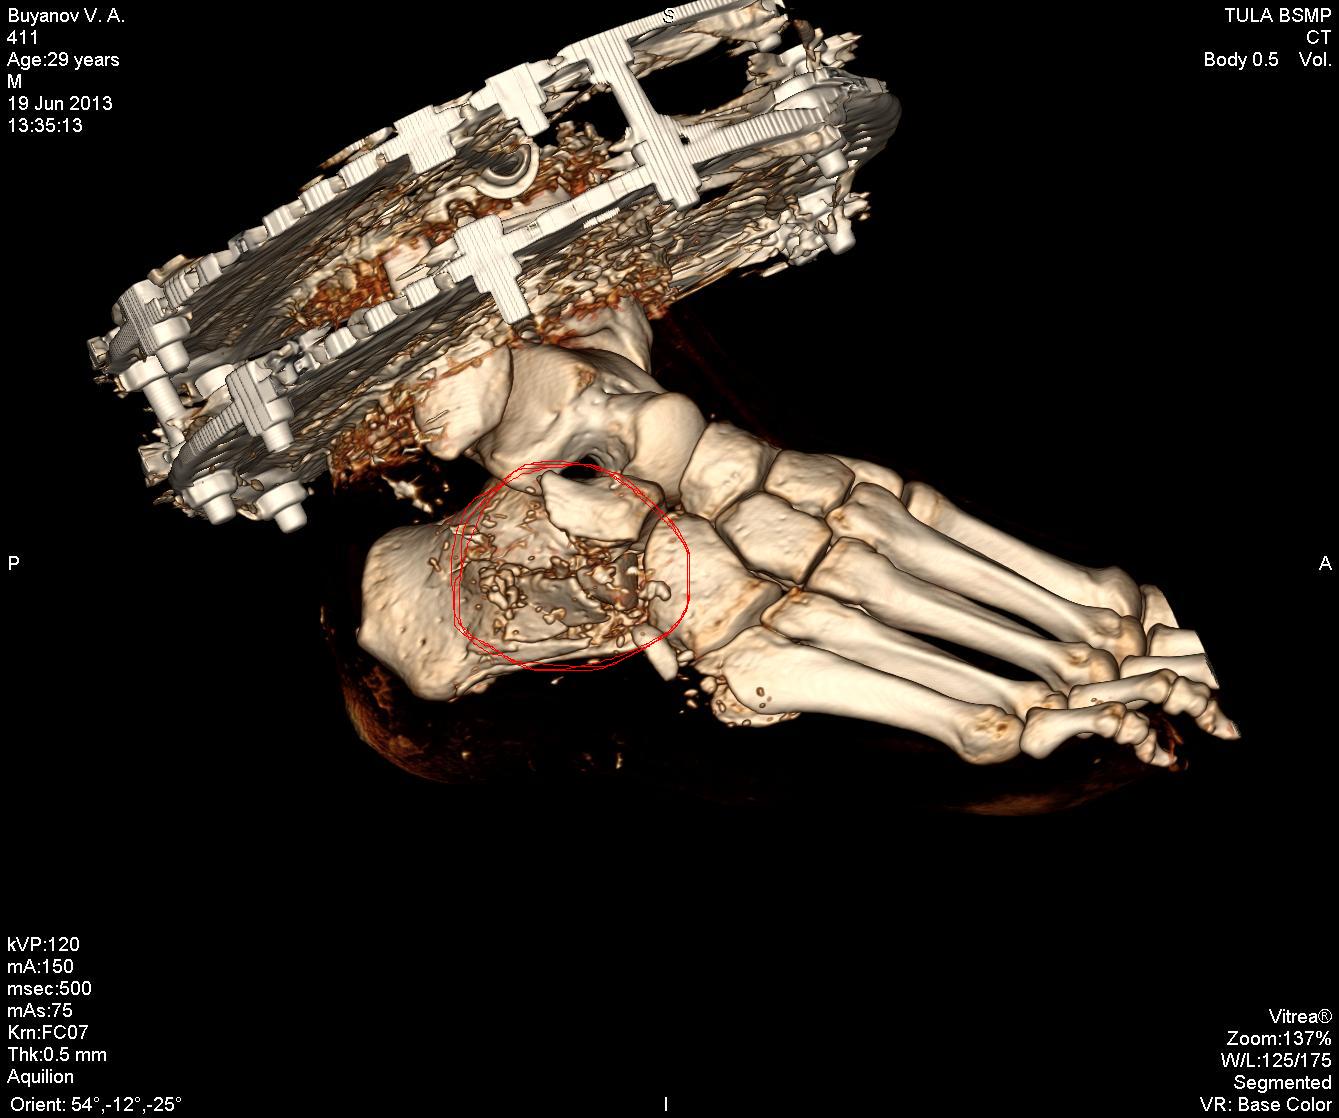

Эпикриз: Сочетанная травма. ЗЧМТ. Сотрясение головного мозга. Открытый многооскольчатый перелом обеих костей с/3 правой голени со смещением отломков. Открытый многооскольчатый перелом пяточной, ладьевидной, кубовидной кости, подвывих пяточной кости. Обширные рваные раны области правой стопы, правой голени.

было это еще 7 июня, но до сих пор, по прошествии двух операций ему не собрали все кости. Оказалосьь, что одну кость забыли на месте ДТП и теперь вместо нее требуется имплант. На одной ноге у него сейчас 18 переломов и 3 из них гниют, один из кусков кости встал поперёк, врачи опасаются её доставать или разворачивать, ибо можно занести ещё больше инфекции, если делать, то надо делать сразу всё комплексно, а пока приходится постоянно чистить, чтоб не было заражения, никакие обезболивающие уже не помогают, организм уже к ним адаптировался, и приходится терпеть эти боли. Нам же остается только медленно собирать деньги.